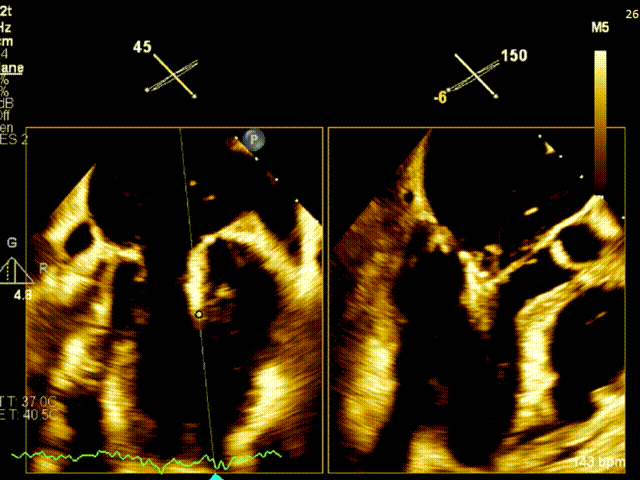

手术过程

患者严重脊柱侧弯,仰卧抬足位于导管床,麻醉成功后。患者仰卧位,常规消毒、辅巾,穿刺左侧颈内静脉置管;穿刺左侧桡动脉测压。穿刺右侧股静胁,植入7F动脉鞘:放置PIG管于右房在房间隔切线位造影(延迟显像暴露LA),在Agilis-s可调弯鞠支持下TEE显示靠近房间隔,上下腔切面tenting不明显。考虑弯度欠佳,更换为Agilis-L可调弯鞘支持下房间隔穿刺鞘再次靠近房间隔,在TEE指导下 conquest pro钢丝连接电刀50/50J,成功穿刺进入左房,以Maverick 2.0*20mm球囊、QUANTUM 4.0*15mm、 QUANTUM 5.0*12mm球囊扩张房间隔,在extention连接钢丝下交换为房间隔穿刺鞘管进入左房,予super stiff置入左上肺静脉,于右股静脉沿super stiff推送MiaClap Guide Catheter G4于左房(因股静脉一右房-左房路径严重迂曲,SGC呈反方向)。于经食道超声指引下,推送XTW Clip Delivery System至二尖瓣左房面(inverted loading),食道超声确认12点钟方向推送至二尖瓣左室面,重新调整DC handle。使Clip Arm至1点钟方向。顺利捕捉二尖瓣前叶A1及后叶P1区域(覆盖脱垂区域),Gripper dowm后关闭Clip Arm 、 经食道超声评估二尖瓣返流量明显减少,确认有效夹持长度,确认瓣叶夹持牢固,释放瓣膜架。经食道超声再次评估二尖瓣返流量<1+,二尖瓣压差1.5mmHg,退出MitraClip系统。

手术结果